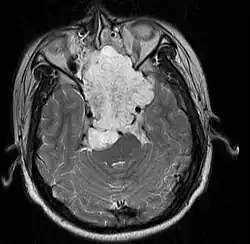

• Skull base:

• May be intracranial or extracranial, with mass effect symptoms depending on location

• Headaches and/or facial pain are common

• Pituitary insufficiency, hemianopsia/diplopia, cranial nerve deficits, nasal stuffiness.

Skull Base